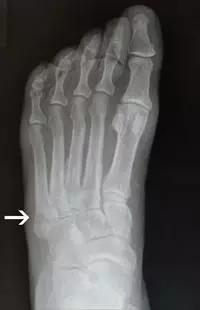

1. Burst 骨折

椎体轴向压力造成的骨折,通常发生骨折碎片向外侧的移位。可以发生在颈椎、胸椎或腰椎。

(来源:Radiopaedia)